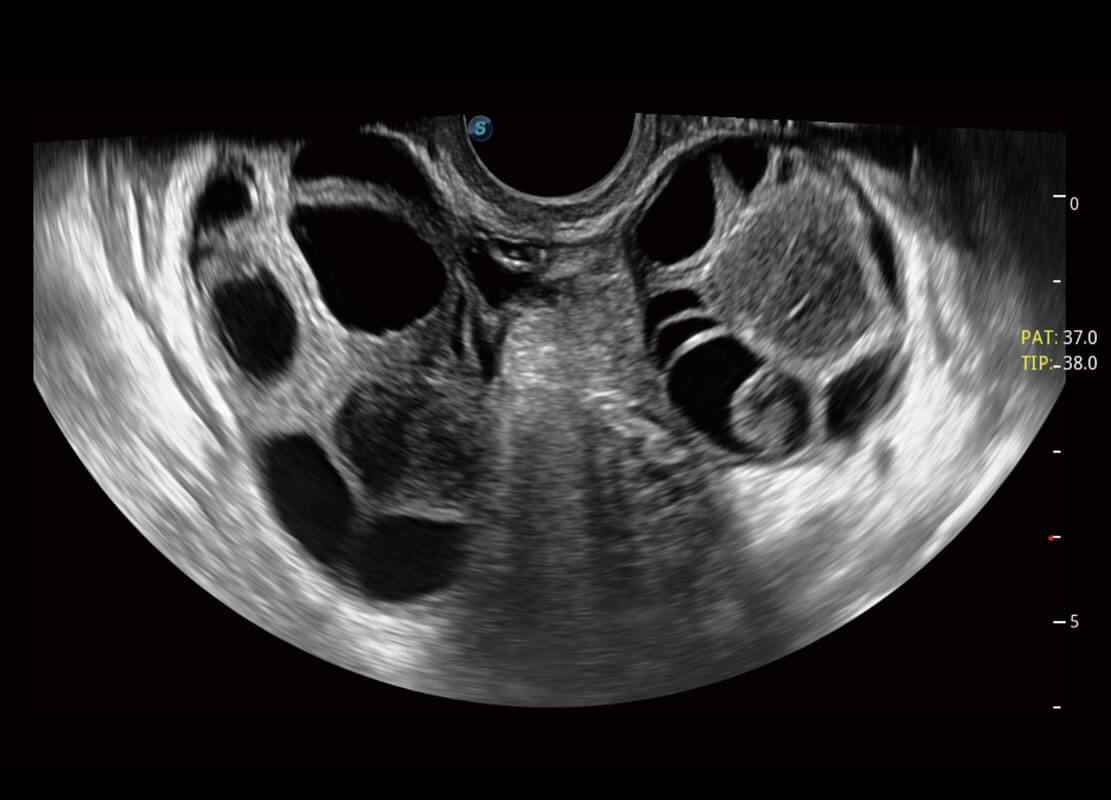

P60优异的图像质量搭载专科探头,在妇科基础疾病的诊断、卵泡生长的监测、输卵管通畅情况的判别等方面为您提供生殖应用方案。

腔内妇科-宫腔分离

腔内妇科-卵巢

腔内三维-宫内节育器